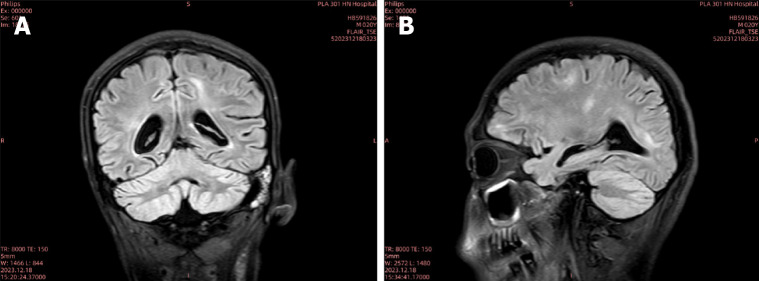

Case summary: A 20-year-old male developed persistent neck and back pain after consuming raw snail meat, followed by urinary retention and low fever. After admission, the patient was misdiagnosed as viral infection and Mycobacterium tuberculosis in central nervous system. After detection of Angiostrongylus cantonensis in blood and cerebrospinal fluid by metagenomics next generation sequencing, albendazole was administered with ceftriaxone and methylprednisolone treatment simultaneously. With effective antiparasitic treatment, the patient weaned from mechanical ventilation successfully and transferred out of intensive care unit for hyperbaric oxygen and rehabilitation treatment.